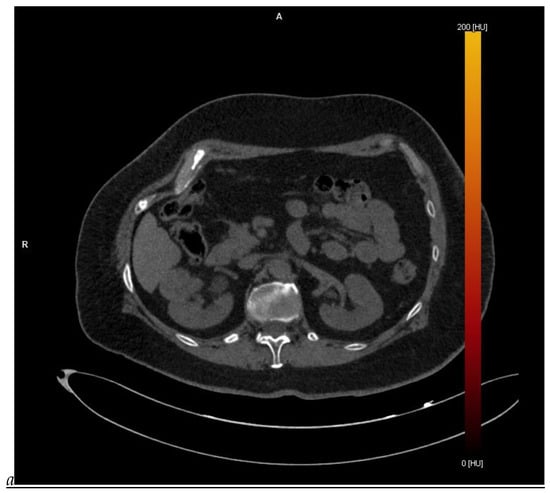

Figure 1.

Dual-energy CT aspect of a hypervascularized clear cell renal cell carcinoma of the upper pole of the right kidney. (a) Virtual unenhanced image. Note the presence of a solid exophytic renal mass in the upper pole of the right kidney. (b) The lesion enhances during the corticomedullary phase; measurement of the iodine concentration of the lesion (4.9 mg/mL) compared to that of the renal cortex (4.2 mg/mL) during the corticomedullary phase. (c) Monoenergetic image obtained at 40 keV during the nephrographic phase. Note the decrease in iodine concentration of the lesion (4.42 mg/mL) compared to that of the renal cortex (6.1 mg/mL). (d) Monoenergetic image obtained at 70 keV during the excretory phase. Compared to the monoenergetic image at 40 keV, the contrast between the lesion and the adjacent renal cortex is reduced. Note the washout of the lesion (iodine content: 1.8 mg/mL).